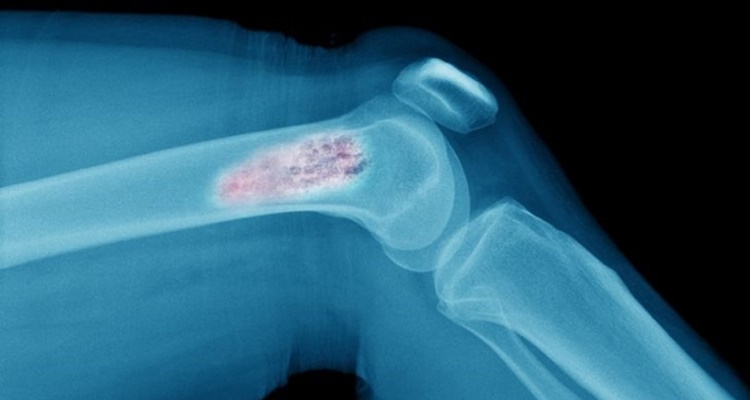

Nadir olarak gözlemlenen ve daha çok diğer kanserlerin metastazı olarak karşımıza çıkan kemik kanseri hakkında farkındalık yaratacak önemli bilgiler…

Yetişkin bir insanın iskelet sistemi 206 kemikten oluşur. İç organlarımızın koruyucusu olarak görev yapar, hareket etmemizi sağlarlar ve kaslarımıza gerekli desteği sağlar. Ancak bazı nadir durumlarda, kemiklerdeki sağlıklı hücreler kontrolden çıkarak tümör olarak adlandırılan bir kitle oluşturarak büyümeye başlayabilir. Kemik kanserine veya kemik neoplazmasına yol açan şey budur. İşte, kemik kanseri hakkında birkaç önemli ancak daha az bilinen gerçekler;

Nadir bir kanser türü olan kemik sarkomu olarak da bilinir ve vücuttaki herhangi bir kemikte büyümeye başlasa da çoğunlukla kol ve bacaklardaki uzun kemiklerde etki görülür. Bir kemik tümörü iyi huylu veya kanserli olabilir. Kanserli bir tümör büyüyecek ve agresif bir şekilde vücudun diğer bölgelerine yayılacaktır. Bununla birlikte, iyi huylu bir tümör büyür ancak vücudun diğer bölgelerine yayılmaz.

Kemik kanserinin olası semptomları arasında, etkilenen bölgede ağrı, ağrının meydana geldiği bölgede şişlik, zayıflamış kemikler nedeniyle oluşan kırıklar, şiddetli kilo kaybı, nefes almada zorluk vb. bulunur. Ancak, bu semptomların çoğu osteoporoz veya artrit gibi durumlarla ilişkili olma eğilimindedir. Bu nedenle, hastalığa nasıl yaklaşılacağı konusunda doktorla görüşmek ve görüşmek en iyisidir.